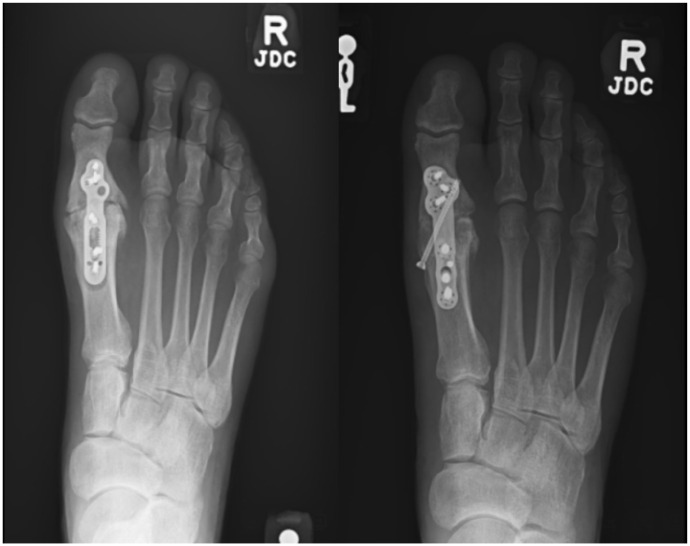

Abstract Image